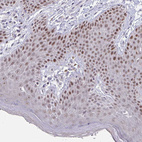

Immunohistochemical staining of human lymph group shows moderate nuclear positivity in germinal center cells.